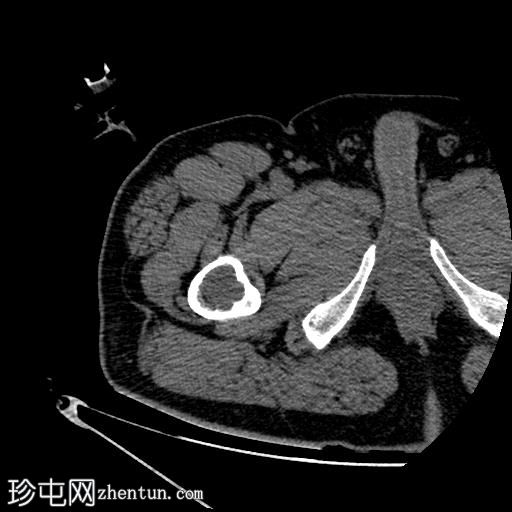

轴位

平扫

右股骨近端干骺端,股骨大转子下方可见一边界清晰的溶骨性病变。

未见皮质破坏及骨膜反应。

将活检针置于右股骨近端干骺端溶骨性透亮肿块中心后,从囊性病变中抽取血液。穿刺活检结果为阴性,未见骨髓浸润。因此,囊性病变的血液样本被送检进行组织病理学检查,结果显示无恶性肿瘤

根据CT影像学表现和组织病理学结果,应考虑右股骨干近端良性囊性骨病变。